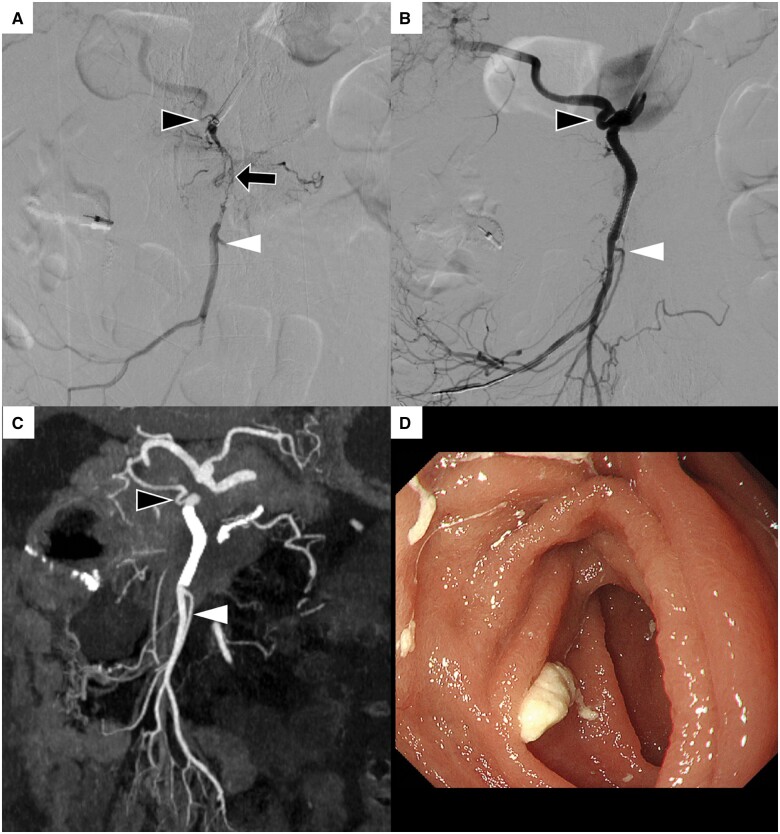

恶性肿瘤侵犯肠系膜上动脉(SMA)是导致肠缺血的一种严重情况。尽管有报道称 SMA 支架植入术可用于动脉粥样硬化斑块引起的 SMA 夹层和狭窄,但针对恶性肿瘤侵犯引起的 SMA 支架植入术却鲜有报道,且效果并不确定。一名 75 岁的妇女因无法切除的胰腺癌侵犯 SMA 而出现肠溃疡和腹泻。针对血管狭窄植入了裸金属支架,支架植入后小肠溃疡明显好转。然而,支架植入一个半月后出现闭塞,于是进行了血栓切除术。血栓切除术后,发现支架因肿瘤侵犯而残留狭窄。血栓切除术后 2 天,患者突然死亡,随后对残余狭窄进行了额外的覆盖支架植入术。对于恶性肿瘤侵犯血管导致的肠道缺血,支架植入可能是一种治疗选择。另一方面,由于肿瘤生长导致的支架再狭窄也是一个问题,为了保证支架的长期通畅,需要考虑覆盖支架。

Superior mesenteric artery (SMA) invasion by a malignant tumour is a serious condition leading to intestinal ischaemia. Although SMA stenting has been reported to be useful for SMA dissection and stenosis caused by atherosclerotic plaque, SMA stenting for stenosis caused by malignant tumour invasion is rarely reported and uncertain. A 75-year-old woman presented intestinal ulcer and melena caused by SMA invasion of unresectable pancreatic cancer. The bare metal stent was implanted for the vessel stenosis, and a small intestinal ulcer was markedly improved after stenting. However, one and a half months after stenting the stent was occluded and a thrombectomy was performed. After thrombectomy, residual stenosis caused by tumour invasion was observed in the stent. The patient suddenly died 2 days after thrombectomy before additional covered stenting for residual stenosis. Stent implantation may be a treatment option for intestinal ischaemia caused by vessel invasion of malignant tumours. On the other hand, re-stenosis of the stent due to tumour ingrowth is a problem, and covered stenting is considered for long-term stent patency.